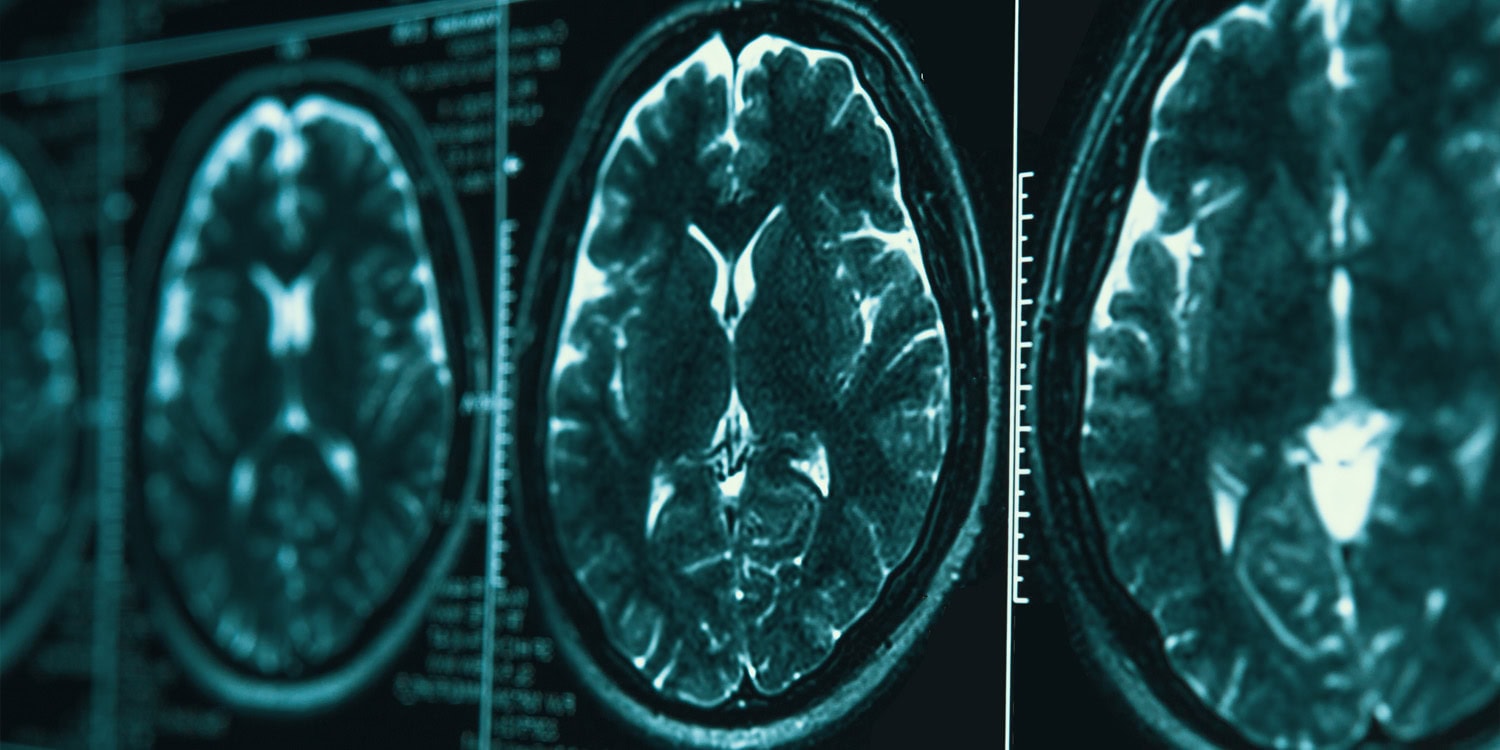

Exposure to indoor air pollution during childhood tends to be linked to poorer cognitive health in older adulthood. This suggests that access to clean energy early in life might help protect the brain as it ages. These findings come from…